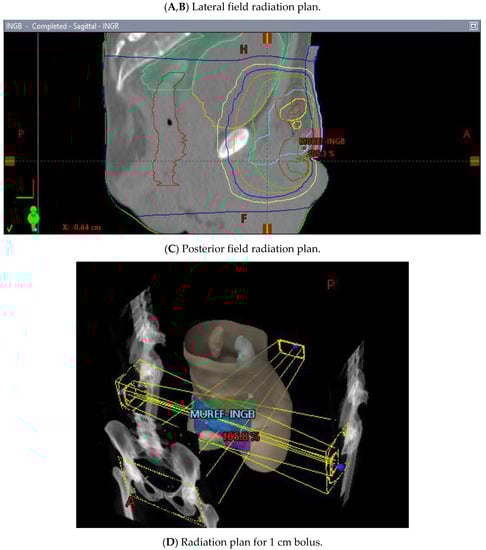

He began dose-reduced FOLFIRI chemotherapy with palliative intent, with the best response being progression after two cycles. His course was also complicated by rapid atrial flutter and hypotension requiring pressors, which were attributed to the progression of the thromboembolic disease, requiring an increase in the anticoagulation dose. Throughout these events, the patient’s principal complaint remained the persistent priapism and associated pain and psychological distress. He was connected to both the palliative care and psychiatry departments and continued follow-up with the urology department, who inserted a suprapubic catheter to reduce the urinary retention. The patient received palliative radiation (20 Gy in 5 fractions) to the groin with the goal of controlling his groin lymphadenopathy, which was thought to be contributing to his priapism (Figure 10A–D). There was a plan to initiate second-line FOLFOX shortly after completing the radiation treatment.

Figure 10.

3 Field (2 laterals (A,B) and 1 posterior (C) field) palliative radiation plan with 20 Gy/5 fractions to the inguinal nodes with a 1 cm bolus (D).